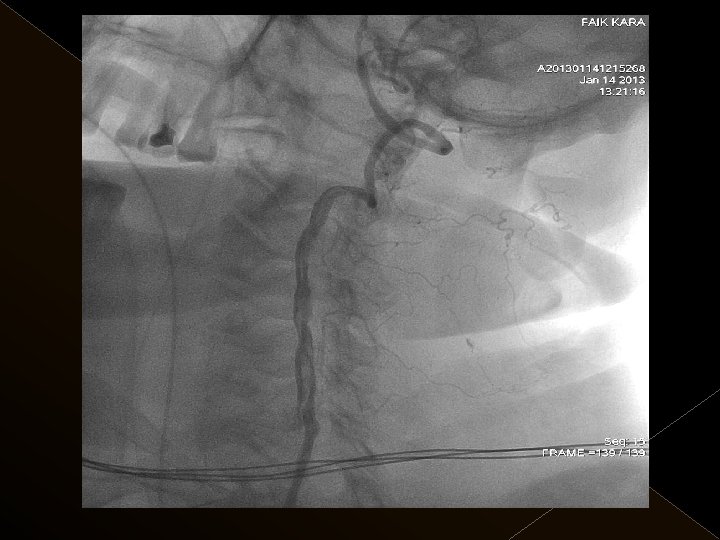

KOMPLİKASYONLAR Ponksiyon bölgesi komplikasyonları � Trombektomi stentine ait komplikasyon (*1) � Diseksiyon(*2) � Karotikokavernöz fistül (‘ 1) � Hemorajik komplikasyonlar(‘ 5) Semptomatik-nonsemptomatik � İskemik komplikasyonlar (3) � Reoklüzyon (2 i. a) � Kontrast madde nefropatisi �